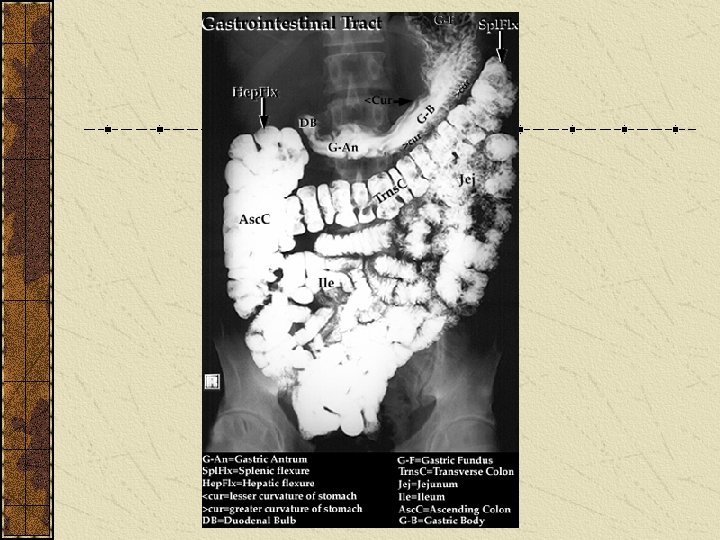

Organ Mouth Teeth Tongue Lips gums Esophagus Stomach Combining Form Stomat/o Dent/o, Odont/o Gloss/o, Lingu/o Cheil/o Gingiv/o Esophag/o Gastr/o

Organ Small intestine Duodenum Jejunum ileum Large intestine Sigmoid colon Combining Form Enter/o Duoden/o Jejun/o ile/o Col/o Sigmoid/o

Organ Rectum Anus and rectum Accessory organs Liver Gallbladder Pancreas Combining Form Rect/o Proct/o Hepat/o Cholecyst/o Pancreat/o